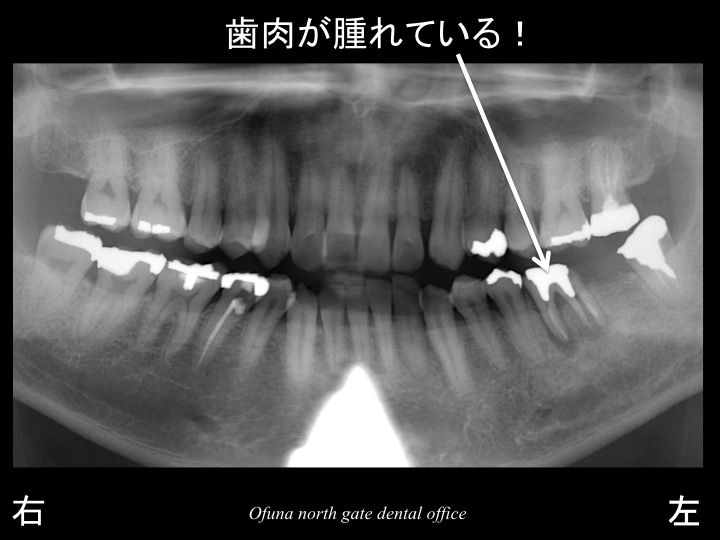

以下は、初診時のレントゲンです。

下顎左側の奥歯が腫れるとのことで来院されました。

歯根破折 を起こすと 歯肉が腫れてきます。

腫れるということは、歯肉の中に膿みが溜まる ということです。

この膿みにより、歯を支えている骨が吸収するのです。

抜歯した部位を拡大して見てみましょう!